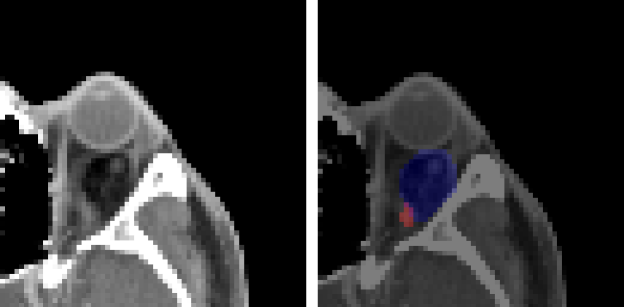

After testing the given CMC-ORBIT dataset, we conducted testing on additional orbital CT data and analyzed the failed case of the proposed methods as shown in Fig. 4. In the case of a Dermoid cyst, when the tumor was blurred in dark, it was not detected. Also, the model does not provide well-segmented results in some specific cases, where the tumor is very small, close to unmarked tissues, and located out of orbit. In the case of Hemangioma, the trained model often failed to detect and segment partially, even though Hemangioma is highly similar to Dermoid cyst in a CT scan. Subsequently, Pleomorphic Adenoma, heterogeneous to Dermoid cyst, is undetectable by the model trained with Dermoid cyst and Hemangioma.